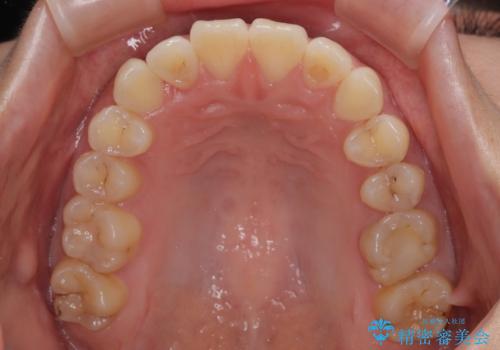

僅か8ヶ月という短期間で、綺麗な歯列に仕上がりました。

- 上下前歯のデコボコを気にして来院された患者様です。

ワイヤー矯正でもマウスピース矯正でも可能でしたが、短期間で、自身の手を煩わせることなく治療を行いたいとのことで、ワイヤー装置にて矯正治療を行うこととしました。